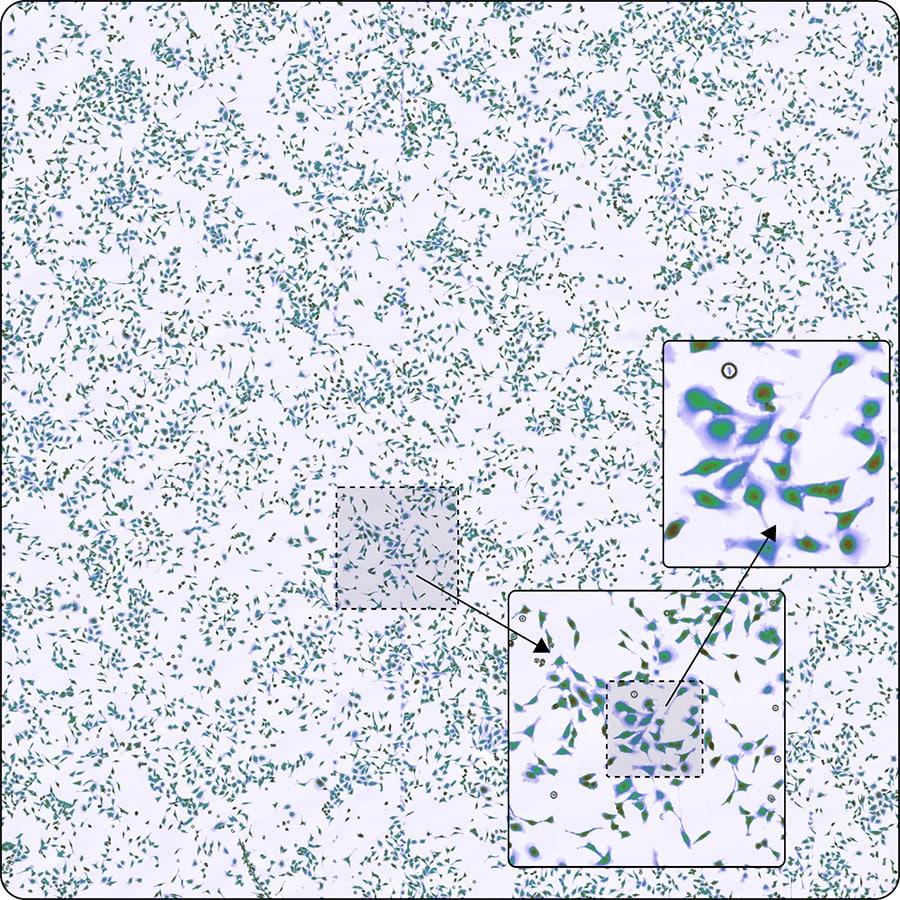

Phototransient holographic imaging builds on quantitative phase imaging (shown here), a microscopy technique that measures light phase shifts as it passes through transparent or semitransparent samples.

At its core, phototransient holography builds upon quantitative phase imaging, a microscopy technique that measures light phase shifts as it passes through transparent or semi-transparent samples. This enables precise assessment of cellular biomass by analyzing light propagation.

Instead of traditional staining methods, such as hematoxylin and eosin (H&E) staining, phototransient holography relies on light interaction with the sample to visualize its molecular composition. The technique integrates holographic imaging, which captures both light intensity and phase, providing researchers with detailed information about sample thickness and composition.

“Taking this a step further, we can spatially resolve cellular mass distribution,” says Liebel. “Standard quantitative phase imaging provides mass information, but it does not reveal chemical composition. Phototransient holography addresses this limitation.”